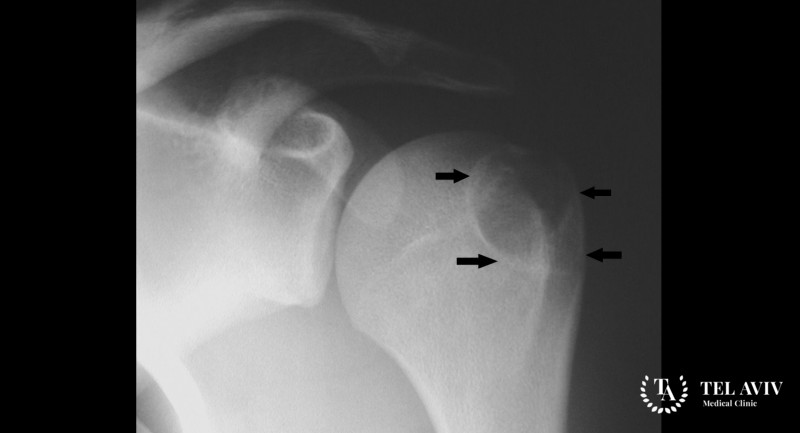

Методы диагностики хондробластомы

Для выявления заболевания необходимо провести ряд гистологических анализов, исследование крови пациента. Из инструментальных методов обследования применяют:

- Рентгенографическое обследование.